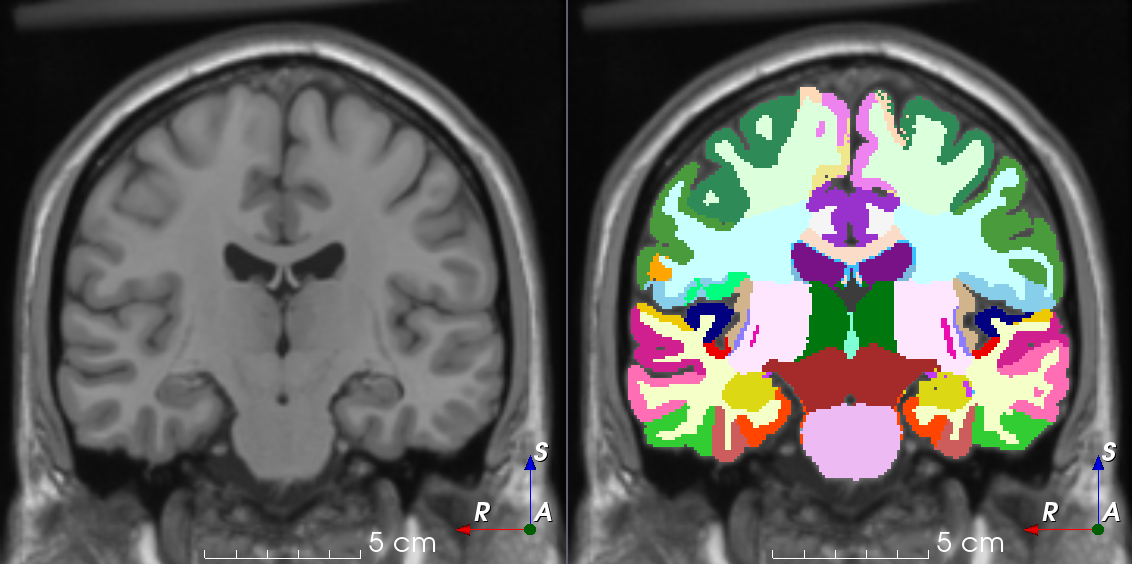

Segmentation

means dividing up an image into different structures

Label Map

each identified structure has a unique ID

Can we segment one human brain and then apply this output to many human brains?

Can this label map be applied to many different scans?

Yes!

Atlas-based Segmentation